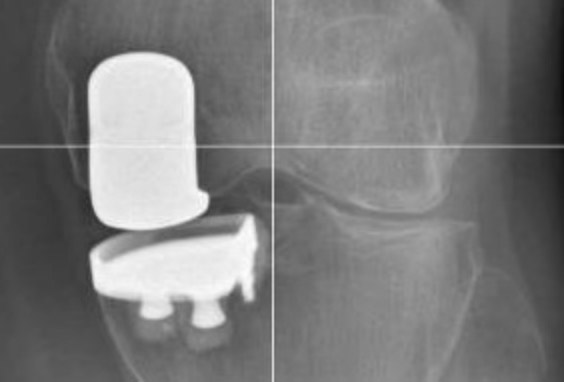

Tecniche Chirurgiche Avanzate:

L’adozione di tecnologie come la chirurgia assistita da computer (CAS) o robotica permette una pianificazione preoperatoria dettagliata e un posizionamento preciso dell’impianto, ottimizzando l’allineamento e il bilanciamento legamentoso. Queste metodiche mirano a personalizzare l’intervento in base all’anatomia specifica del paziente, migliorando gli esiti funzionali e la longevità della protesi.

Vantaggi Rispetto alla Protesi Totale:

Quando indicata, la protesi parziale di ginocchio offre numerosi vantaggi rispetto alla protesi totale, tra cui minore invasività, recupero più rapido e migliore funzionalità articolare. Tuttavia, è essenziale una valutazione accurata per determinare l’approccio più appropriato per ciascun paziente, garantendo così i migliori risultati possibili.